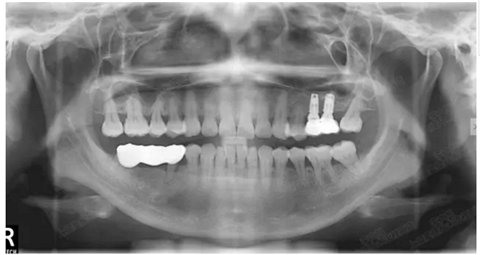

病例二

剩余骨量2mm

003.png

提升10mm

004.png